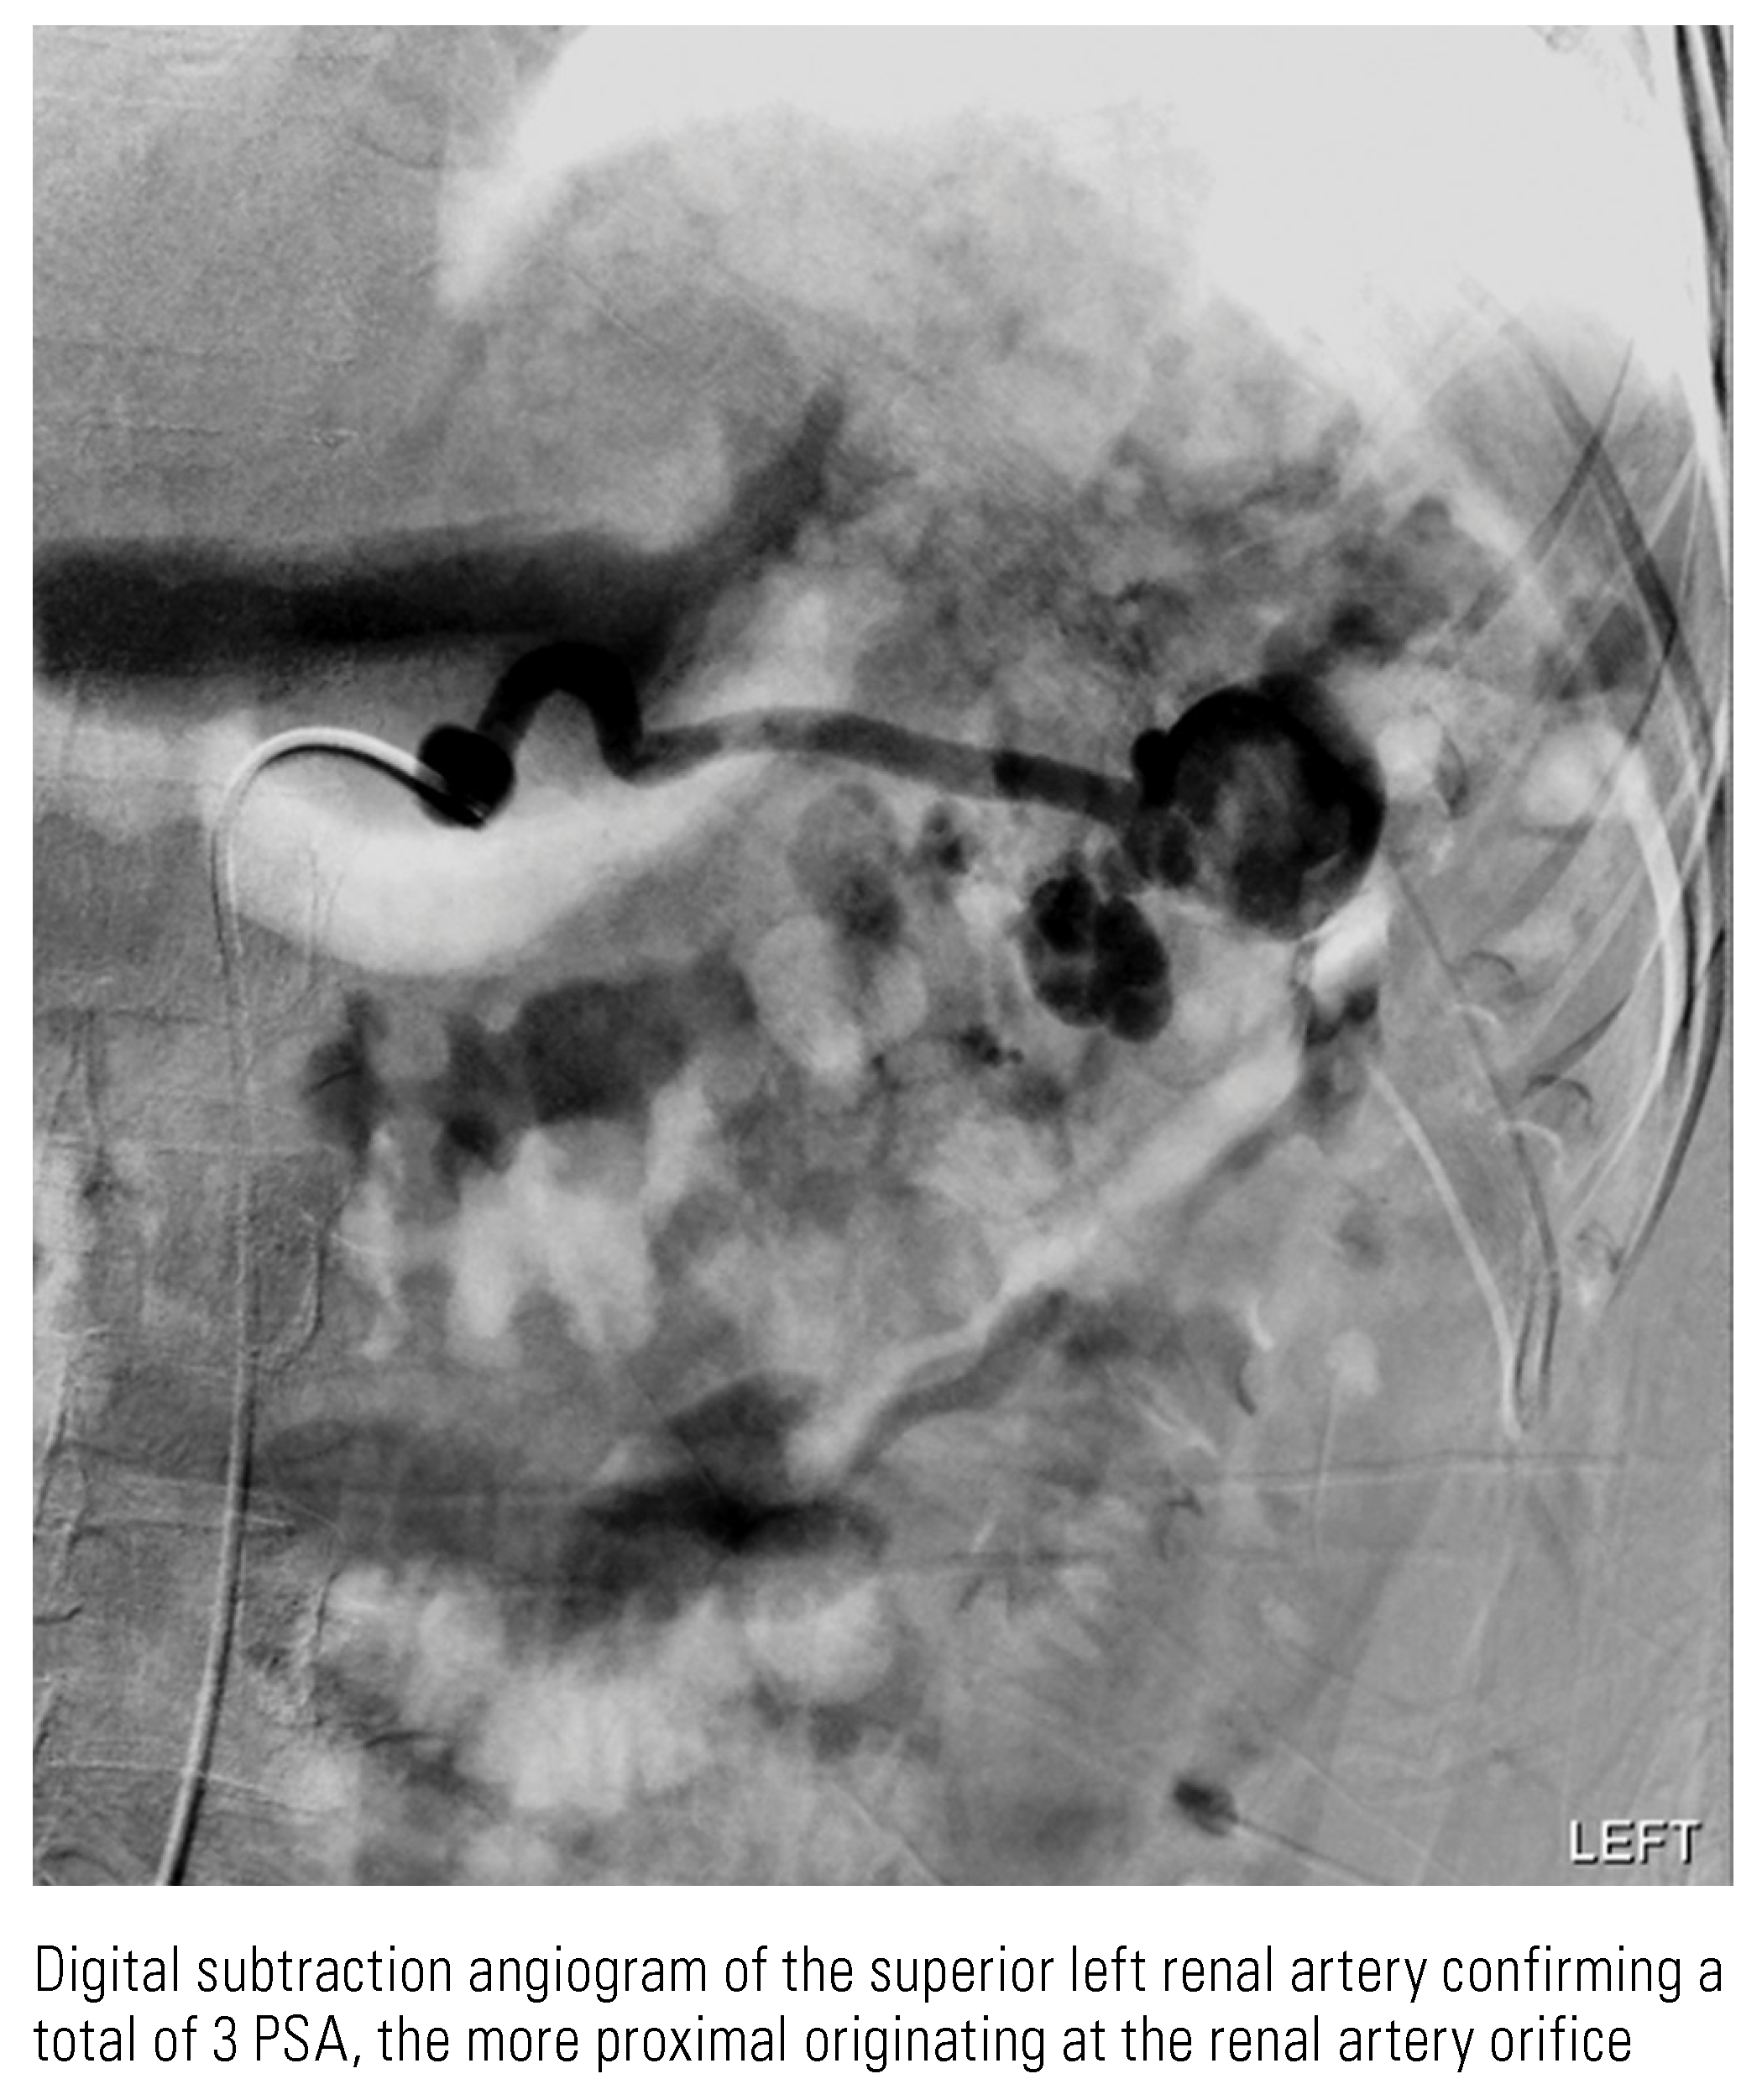

Renal Cell Carcinoma with Intratumoral Pseudoaneurysm